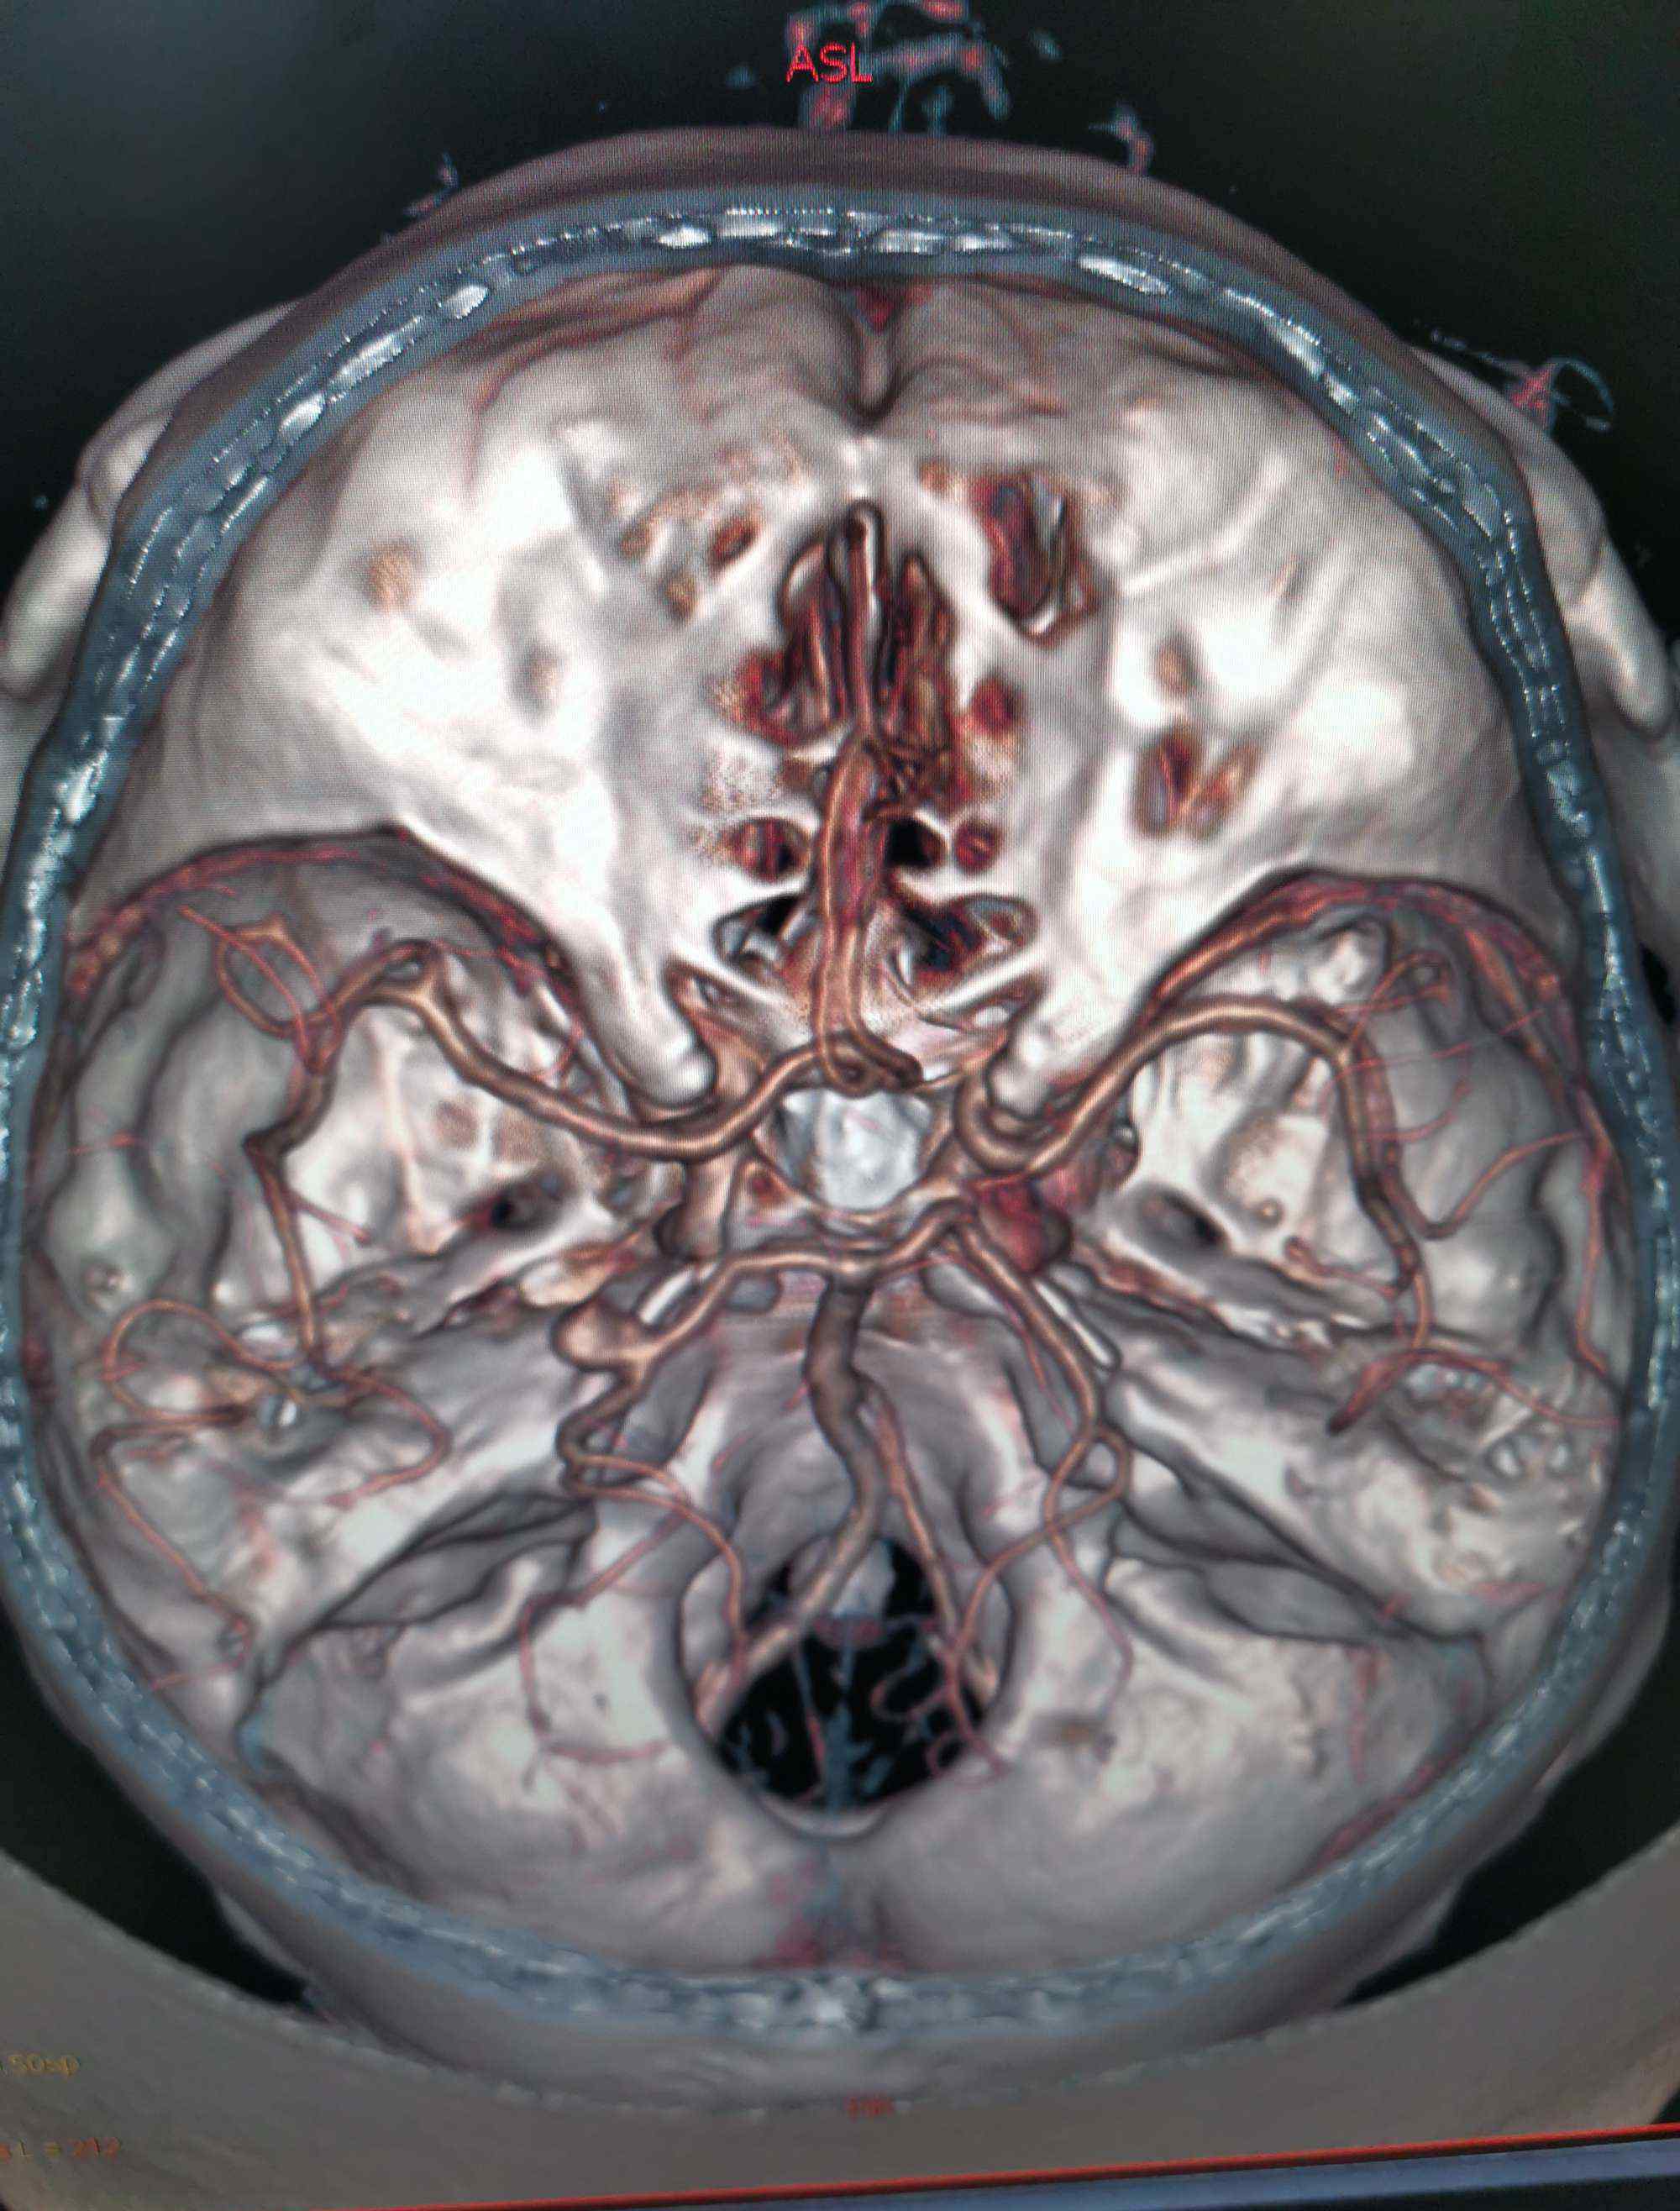

入院后行CTA,考虑左侧后交通动脉瘤。但局部高密度影,考虑动脉瘤破裂出血或巨大动脉瘤附壁血栓可能性大。

考虑为宽基底4.9毫米,大小约为7.9*7.1毫米。